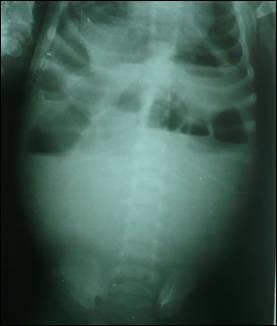

Figure 1: Abdominal radiograph suggestive of mass effect and intestinal obstruction.